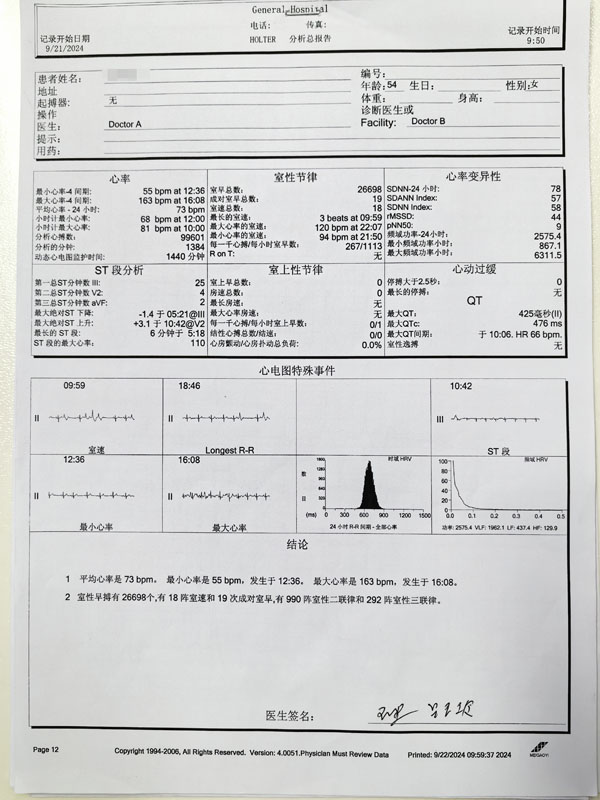

患者史女士主诉心慌、气短伴头晕,偶有胸痛、背痛10余天,已就诊两家医院,症状未得改善,遂就诊于我院心血管内科。患者12导联心电图示,“窦性心律,频发室性期前收缩”;心脏彩超提示,“检查过程中可见频发期前收缩,二尖瓣轻度关闭不全”;24小时动态心电图示,“最大心率为163次/分,室性早搏26698个,有18阵室速和19次成对室早,有990阵室性二联律和292阵室性三联律”。

患者24小时动态心电图